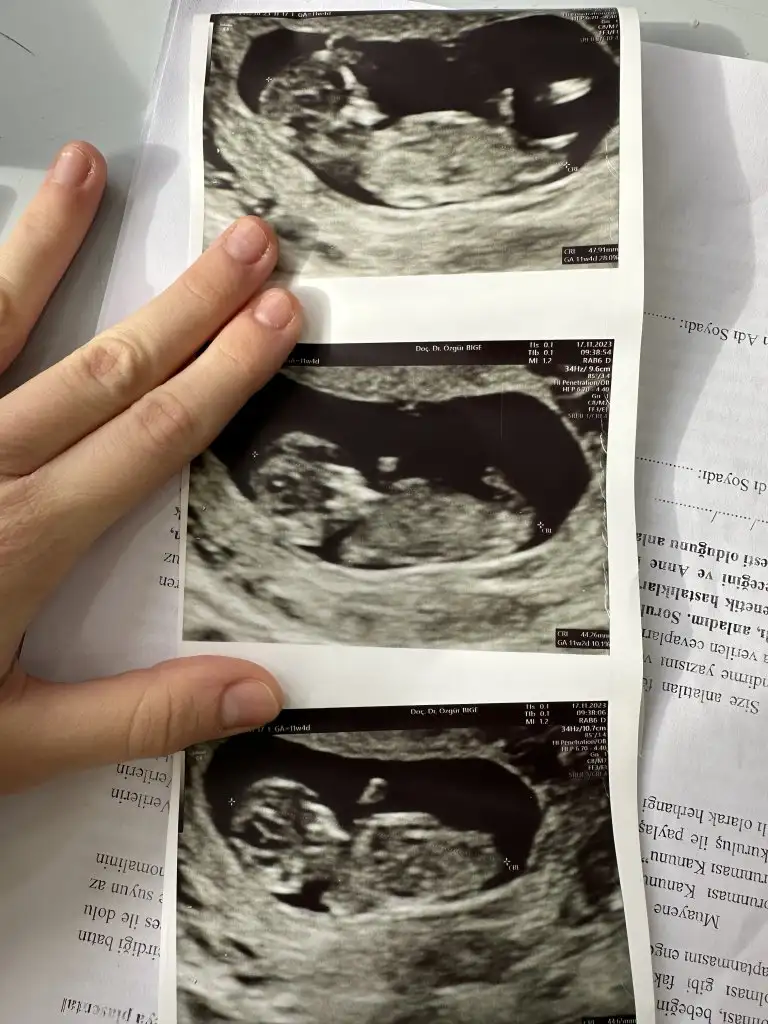

Sırayla 8-12-14 hafta hepsi karından yorumlarsanız sevinirim

12 haftalıkken erkege benziyor denildi 14 hafta kıza benziyor denildi 15 haftalık oldum hala bilmiyorum bebisimin cinsiyetini dahada doktora gitmeme 3 hafta var meraktan çatlamak üzereyim 😅